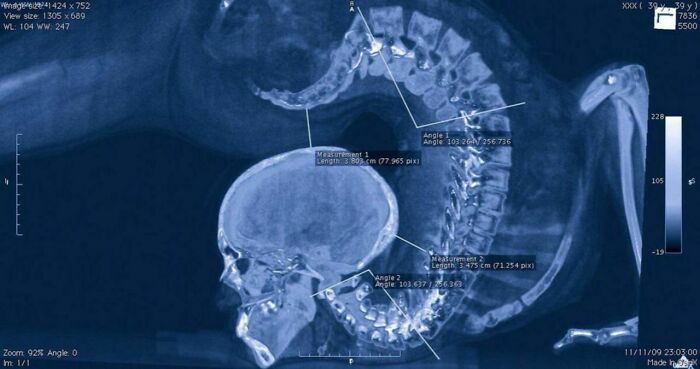

Рентген гимнастки, выполняющей упражнение

Доказательство того, что люди немного скорпионы 🦂

Если вы когда-нибудь хотели примерить свою попу в качестве шляпы, то вам прямая дорога в гимнастику 🤸♀️